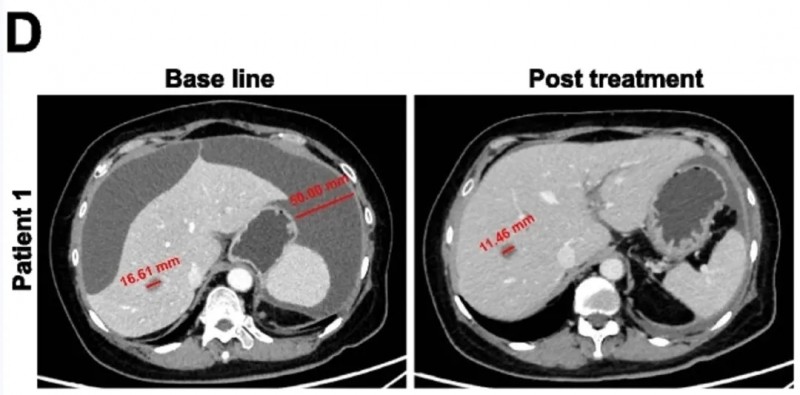

此外,CAR-GPC3 T细胞治疗2周后,患者腹膜后淋巴结转移灶(LM)开始缩小,病变短轴直径缩小5.2%、长轴直径缩小4.5%;第7次输注后第7天,靶病变短轴进一步缩小7.4%(详见下图H-I)。后续患者接受伽玛刀放射外科治疗(GKRS)后,AFP水平逐步降至正常范围,且自此进入无癌状态。除2016年7月的GKRS治疗外,患者未再接受任何抗癌治疗,仍保持无病状态超5年,总生存期超8年(详见下图,注:红色箭头表示治疗后的坏死肿瘤)。

▲图源“WILEY Online Library”,版权归原作者所有,如无意中侵犯了知识产权,请联系我们删除